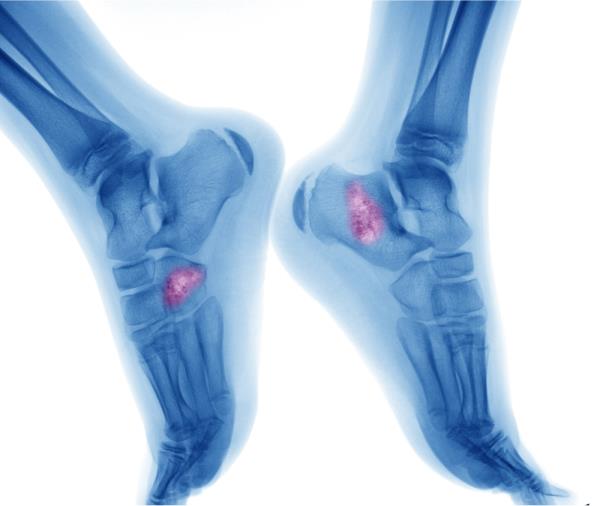

Diagnosis of Multiple Myeloma

Imaging tests can not only diagnose MM but help determine the extent of disease throughout the body, its locations and how active it is. X-rays, magnetic resonance imaging (MRI), and positron emission tomography (PET) may be used for this.

Bone marrow aspiration and needle biopsy may also be used to show the percentage of plasma cells in the bone marrow.